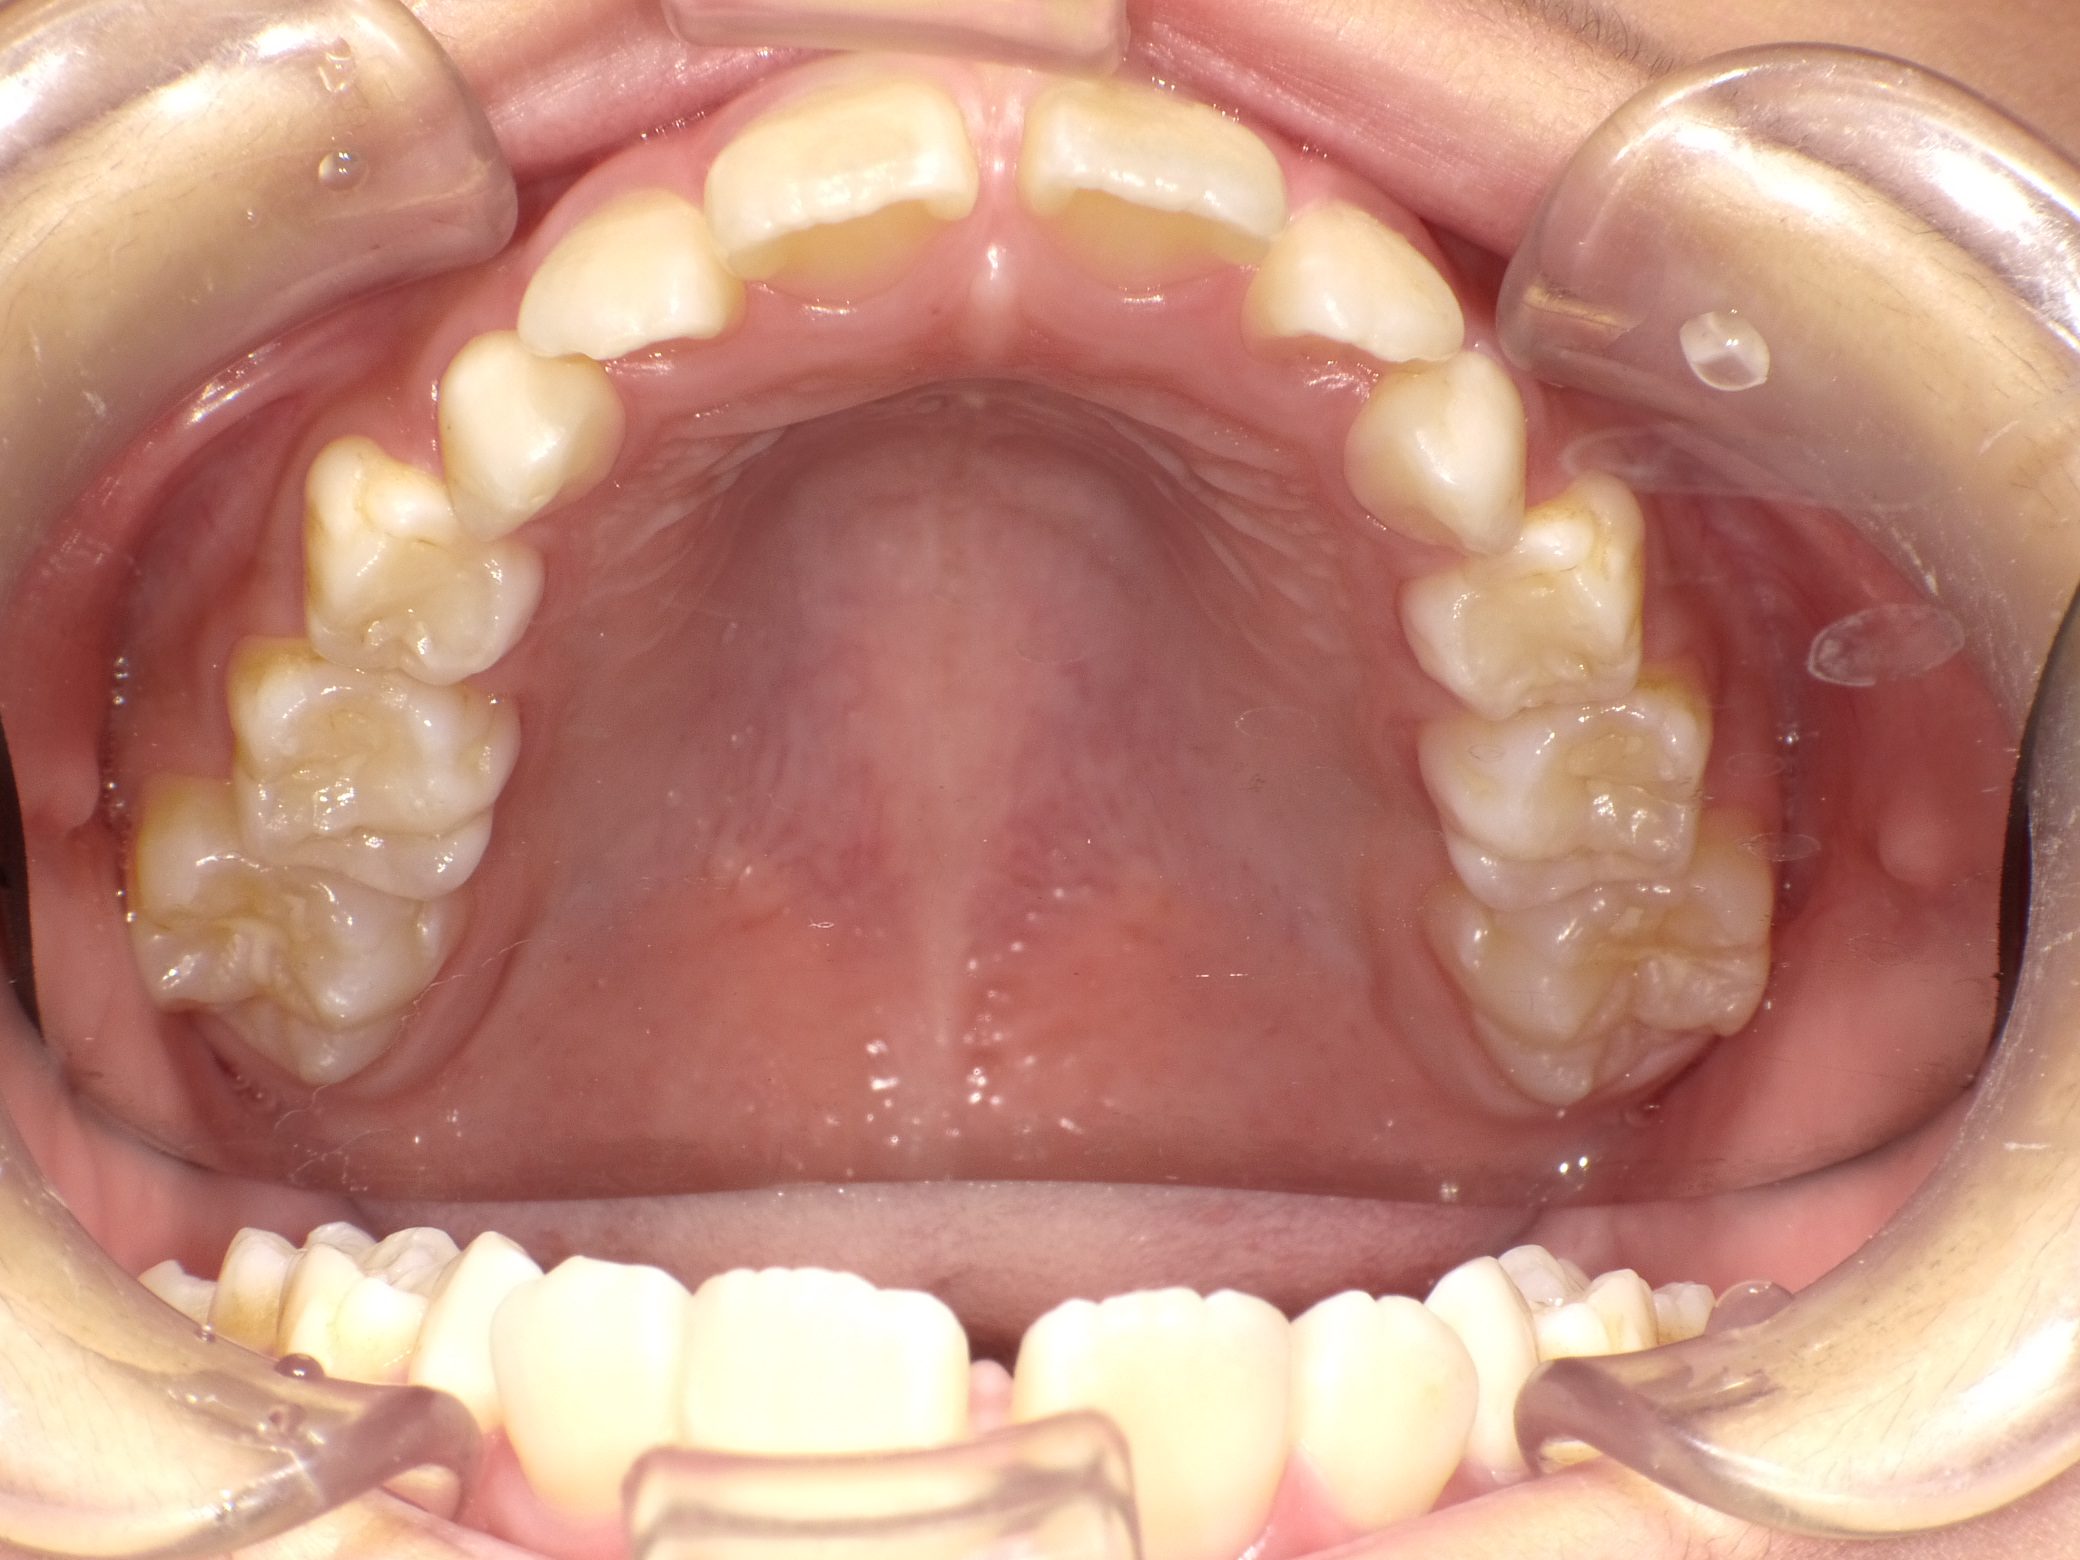

Before

After

舌癖が原因で、前歯が動揺していましたが、矯正治療を開始して動揺は収まりました。

矯正後、写真撮影時は 外傷で歯を打って動揺が出た時期だったため、 後ろから固定しています。

afterの写真は全て永久歯列になった時の写真です。